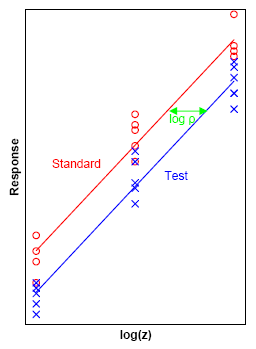

An antibiotic standard (shown in red) and test preparation (shown in blue) are applied at three dose levels to sensitive microorganisms on a layer of agar in petri dishes. The stronger the dose the larger the zone of inhibition of growth of the microorganisms. The biological response  is in this case the zone of inhibition and the diameter of this zone

is in this case the zone of inhibition and the diameter of this zone  can be used as the measurable response. The doses

can be used as the measurable response. The doses  are transformed to logarithms

are transformed to logarithms  and the method of least squares is used to fit two parallel lines to the data. The horizontal distance

and the method of least squares is used to fit two parallel lines to the data. The horizontal distance  between the two lines (shown in green) serves as an estimate of the potency

between the two lines (shown in green) serves as an estimate of the potency  of the test preparation relative to the standard.

of the test preparation relative to the standard.